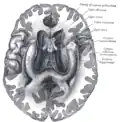

Coronal section of brain immediately in front of pons.